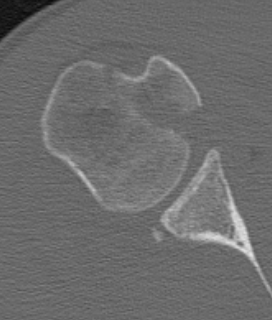

CT scan

Confirms dislocation

Reverse Hill Sachs

Humeral head defect

- caused by impaction of anterior humeral head on posterior glenoid

- intra-articular

- measured as a percentage of the articular surface

Lesser tuberosity fractures

Posterior glenoid fractures / bony bankart